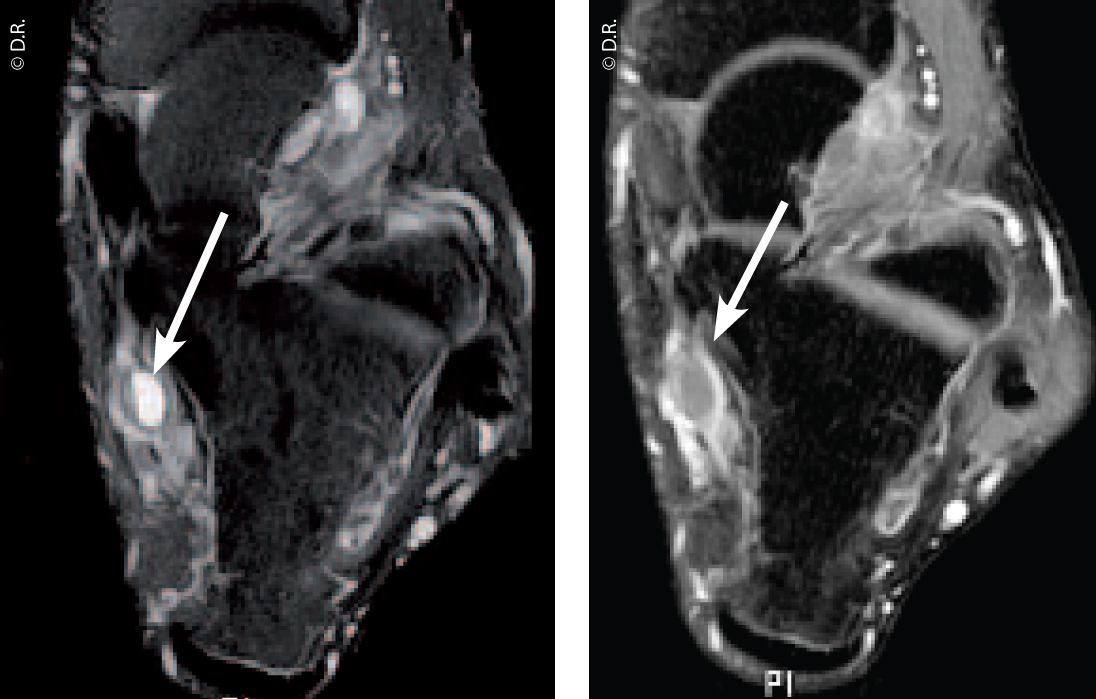

Angiome des parties molles